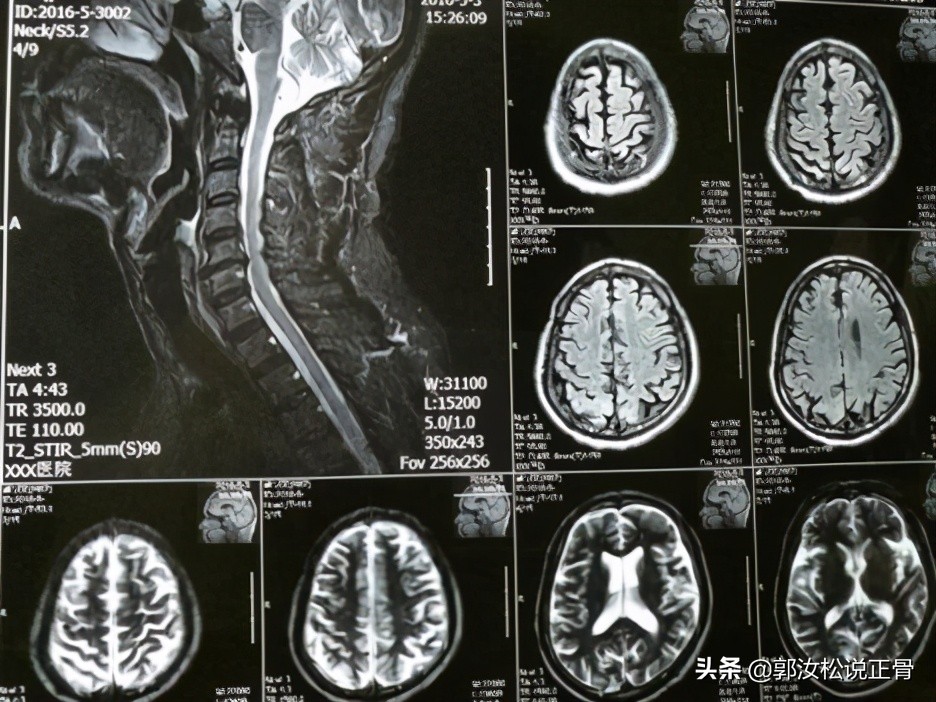

现病史: 1年前患者开始出现颈部不适,伴有头晕,发作时无天旋地转感,无恶心呕吐,无胸闷心慌,无耳鸣,走路时有不稳感,无四肢麻木,无四肢无力,随到当地医院就诊,给予颈椎MR及头颅MR检查提示:颈椎退行性变,C5/6椎间盘突出,相应层面硬膜受压,脊髓轻度受压,脊髓未见明显变性;头颅未见明显异常。当时诊断颈椎病,给予药物治疗,疗效不佳,后建议患者手术治疗,患者拒绝,随来我院我科就诊:颈部酸痛,头晕,走路不稳感,无恶心呕吐,无胸闷心慌,无四肢麻木。

/ / 诊断:混合型颈椎病 //颈椎和头颅MR